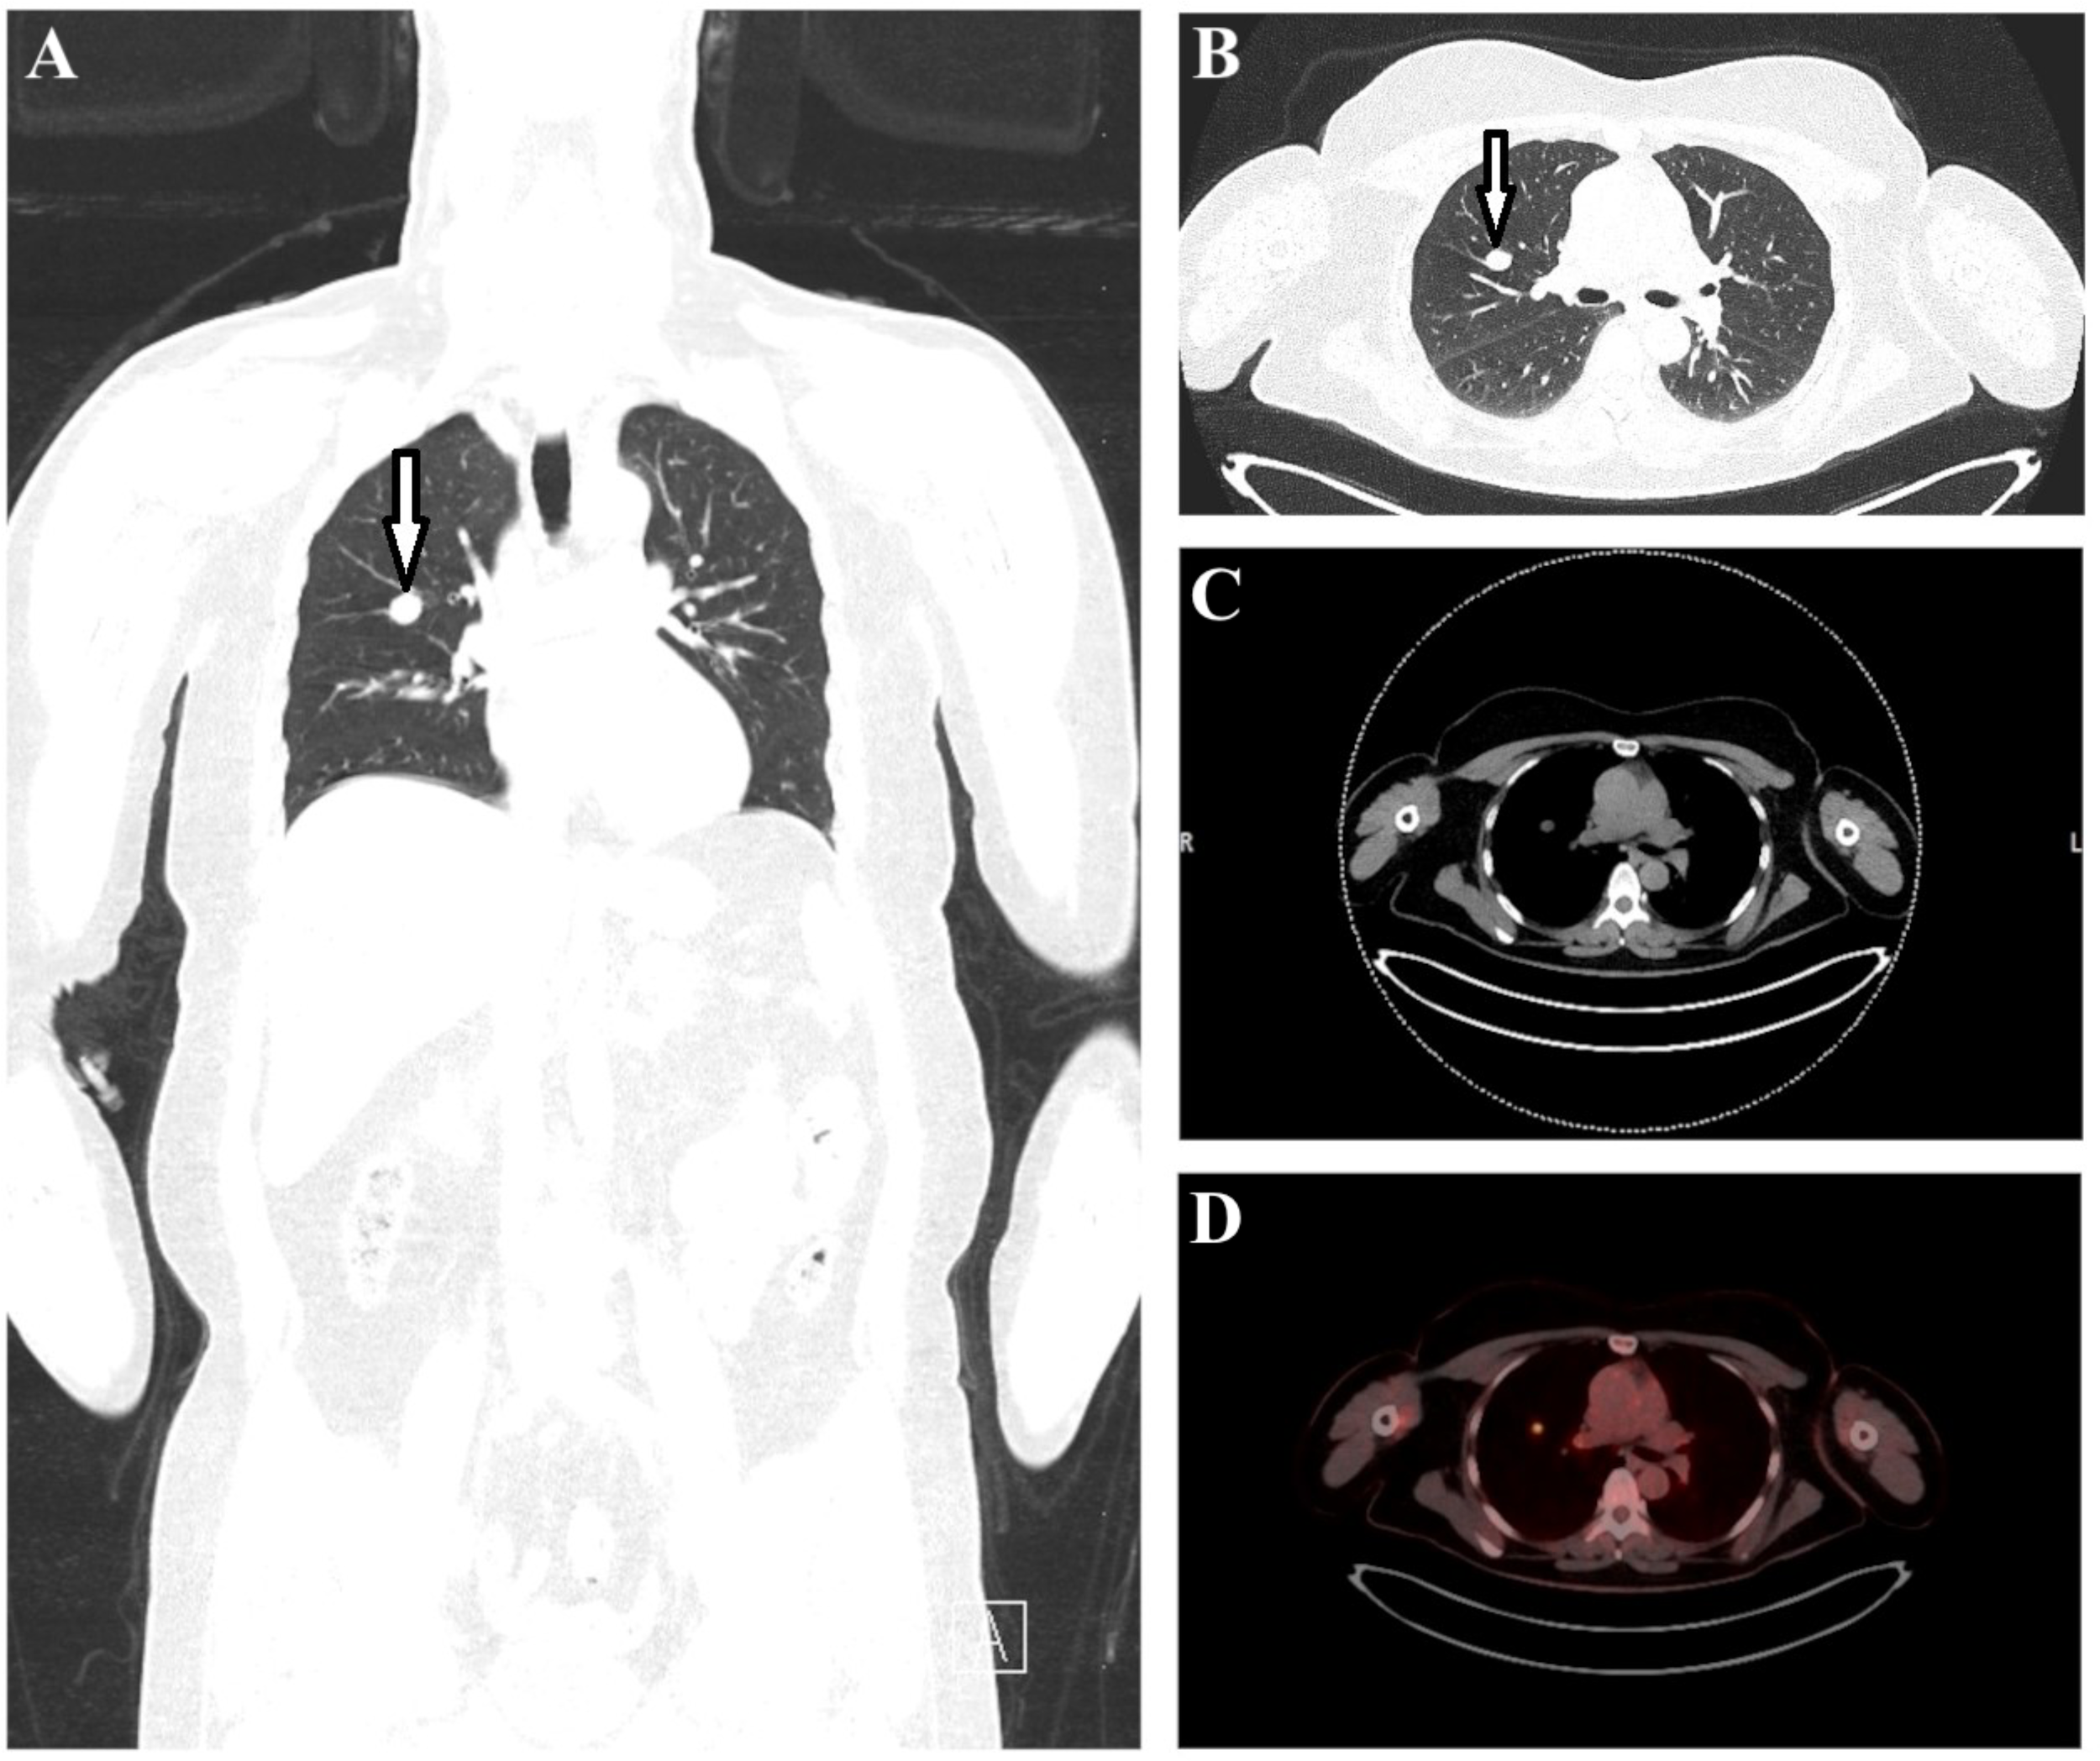

The multiplanar reformate image (MPR) and lung CT revealed a 16 mm x 12 mm mass in the right upper lobe (Figures 2A, B, marked by arrows). In accordance with this, axial CT soft tissue window (Figure 2C) and transaxial fused PET-CT image (Figure 2D) showed an increased focal 18F-FDG uptake (SUVmax 6.3) in the right upper lobe adjacent to the hilus. In addition, a bilateral diffuse enhancement with mild focal emphasis cranially of the hilus (left SUVmax 5.8 > right SUVmax 4.8) was detected. The radiological findings revealed an urgent suspicion of lung carcinoma in the right upper lobe parahilar without pathologic lymph nodes. For bioptic/histological clarification, the patient was then referred for presentation to a pneumological/thoracic surgery center.

Figure 2

The multiplanar reformate image (A) and lung CT (B) revealed a 16 mm x 12 mm mass in the right upper lobe (marked with arrows). Axial CT (C) and transaxial fused PET-CT image (D) showed an increased focal 18F-FDG uptake (SUVmax 6.3) in the right upper lobe parahilar.